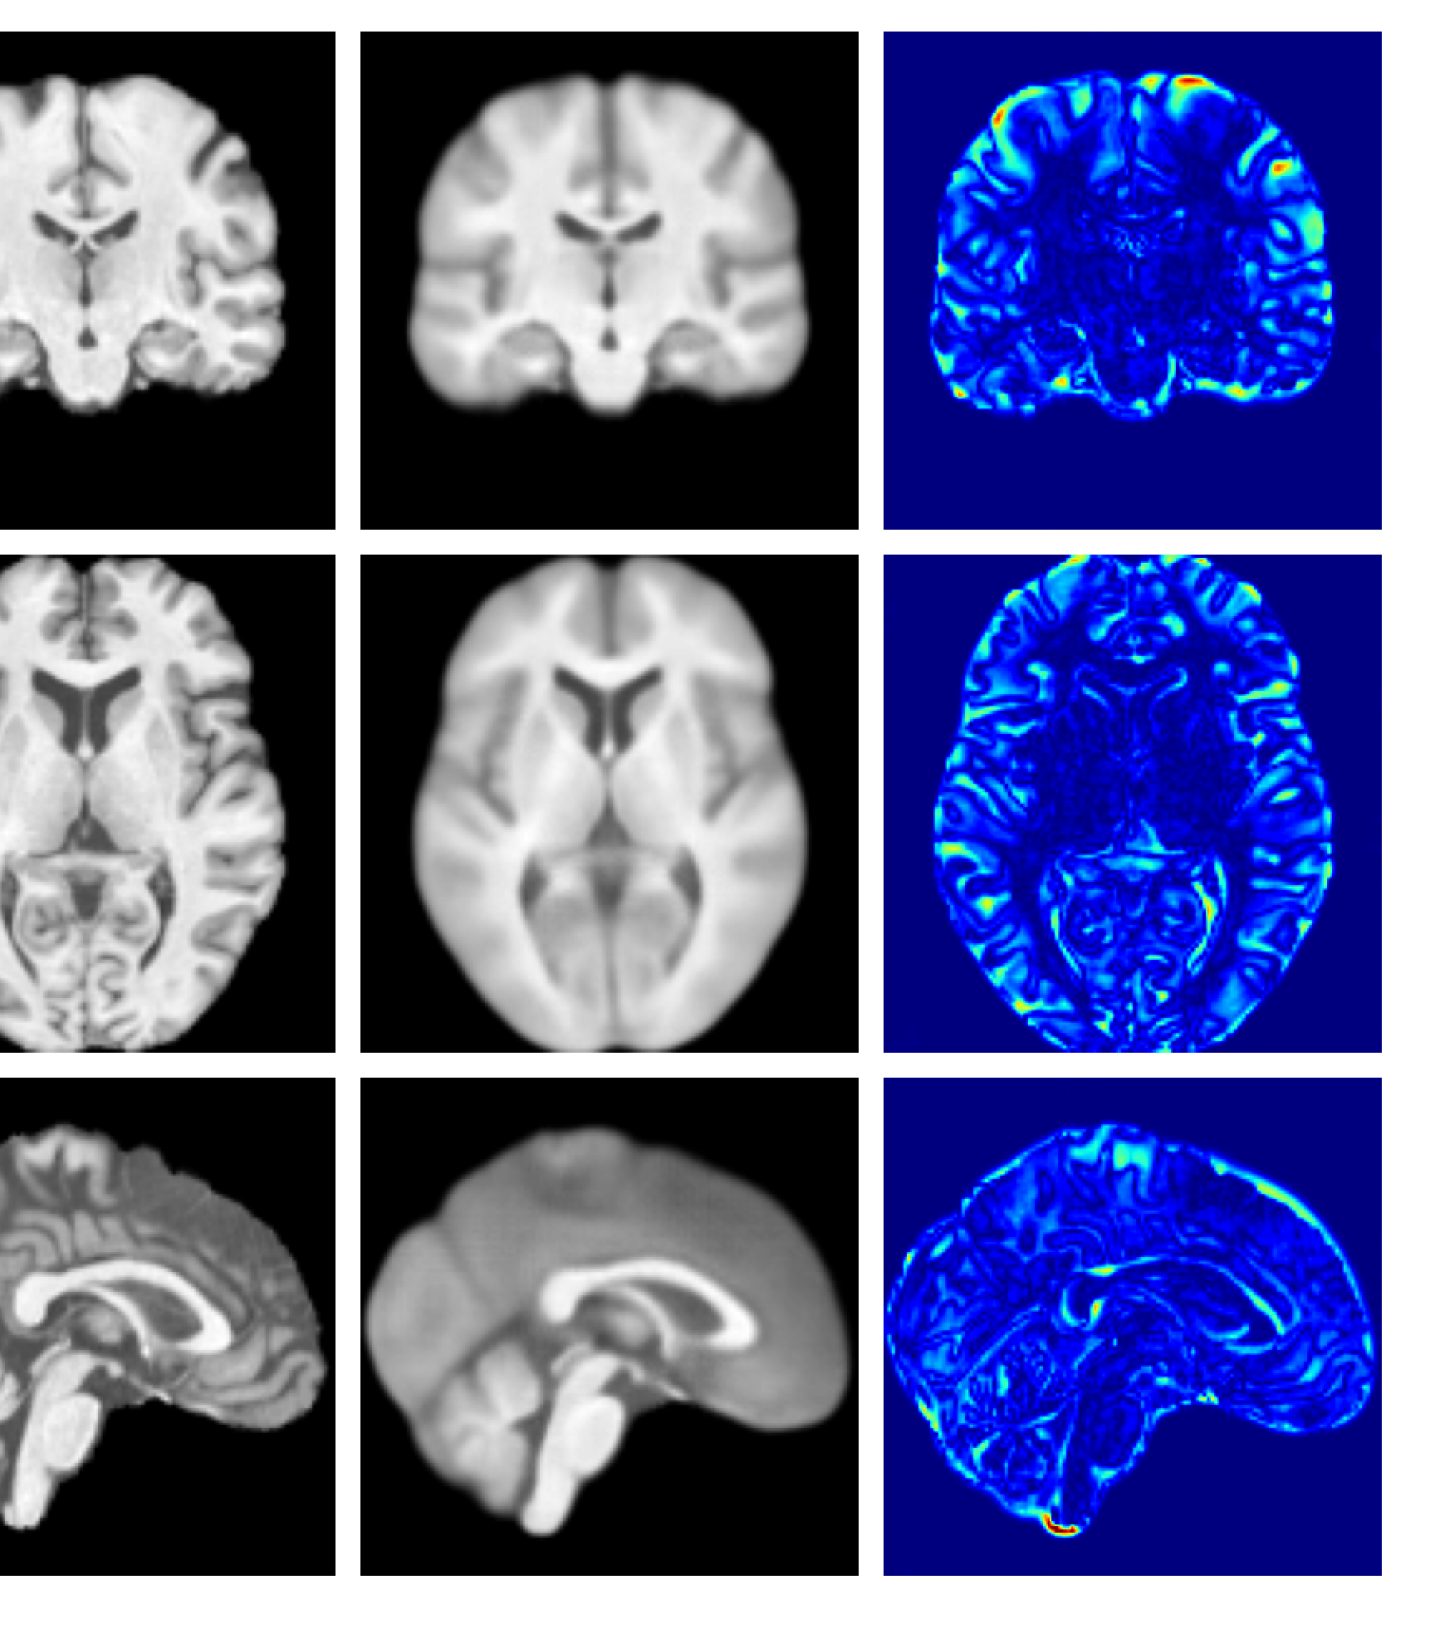

Figure 4: Example reconstructions and anomaly maps from a disease cohort sample in the UoTH dataset, shown for the top three models. The lesion is highlighted in red in the original image.

For the UoTH dataset, Table 2 shows that whilst CADD outperforms all other DDPM methods, it is outperformed by the VAE and cVAE models. Unlike the UKBB and ADNI datasets, the UoTH dataset contains noisy images with larger lesions and regions of pathology. Here, the CADD threshold, which limits the number of regions flagged as anomalous at each inpainting step, may be too stringent to fully inpaint extensive anomalies. It should be noted, however, that the improved disease detection performance of the VAE and cVAE models comes at the cost of accurate reconstruction of healthy tissue as illustrated in Table 1 and Figure 4. Such poor quality reconstructions would not be suitable for downstream tasks such as anomaly segmentation or image processing algorithms.

Figures 8 and 9 are enlarged versions of Figures 3 and 4 respectively, with the latter now including results from all compared methods. Figure 10 provides example reconstructions and anomaly maps for an AD subject from the ADNI disease cohort.

Figure 9: Enlarged example reconstructions and anomaly maps for a sample from the disease cohort of the XXXH dataset. The lesion region is indicated in the original image by the red box.